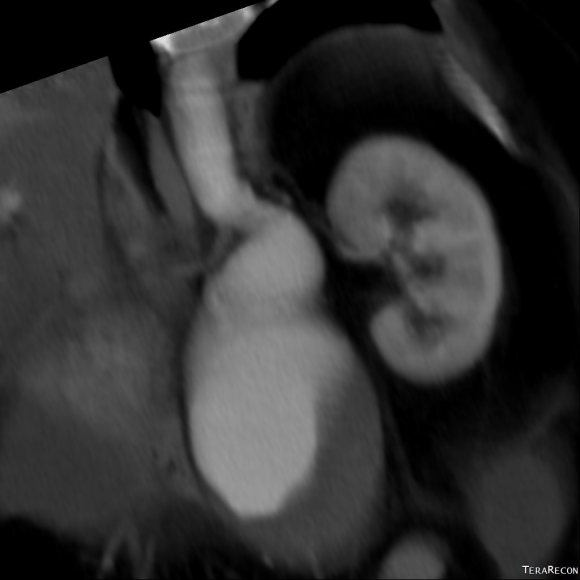

CT scan was performed showing an enlarging AAA over 8am and abundant retroperitoneal pancreatic fluid without abscess or infection. The AAA was infrarenal but complicated by a severely tortuous, short infrarenal neck with 90 degrees of angulation and about 8mm in length. As the pancreatic leak was yet early in the process, no pseudo aneurysms had formed. MRCP showed no active leak.

2. EVAR -This is outside the IFU for any of the available devices because of the highly tortuous neck anatomy. While note shown, the external iliac arteries were 5mm in diameter, but in the absence of plaque, was possibly due to spasm. The Nellix device is yet on trial, but there are limits on how much you can straighten this neck. The devices with suprarenal stents end up straightening out the graft with deployment of the graft in an ellipse. This also means loss of seal zone length which decreases with oblique deployment. FEVAR is not possible because of this neck tortuosity as well but was considered briefly.